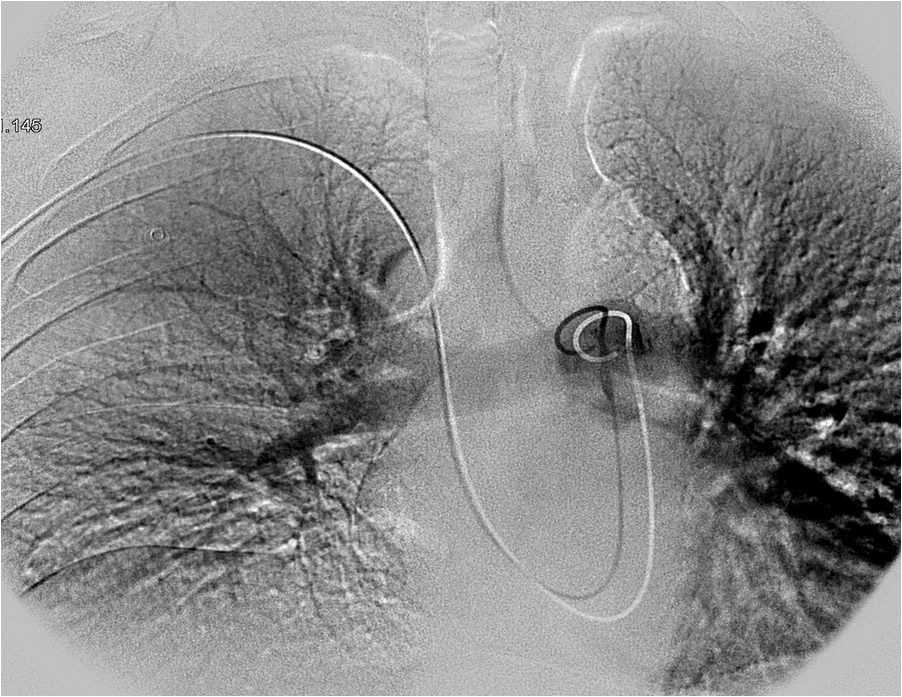

Transcatheter coil embolization. (a) A complextype PAVM with three Catheter Embolization Therapy Arterial embolisation cannot cure the cancer by itself. What is a vascular embolisation? You may be offered arterial embolisation if an operation is not possible for you. Chemoembolisation is a treatment directly into the liver. The embolization procedure is done by inserting a catheter through an artery that feeds the liver and inserting a substance that blocks blood flow to. Catheter Embolization Therapy.